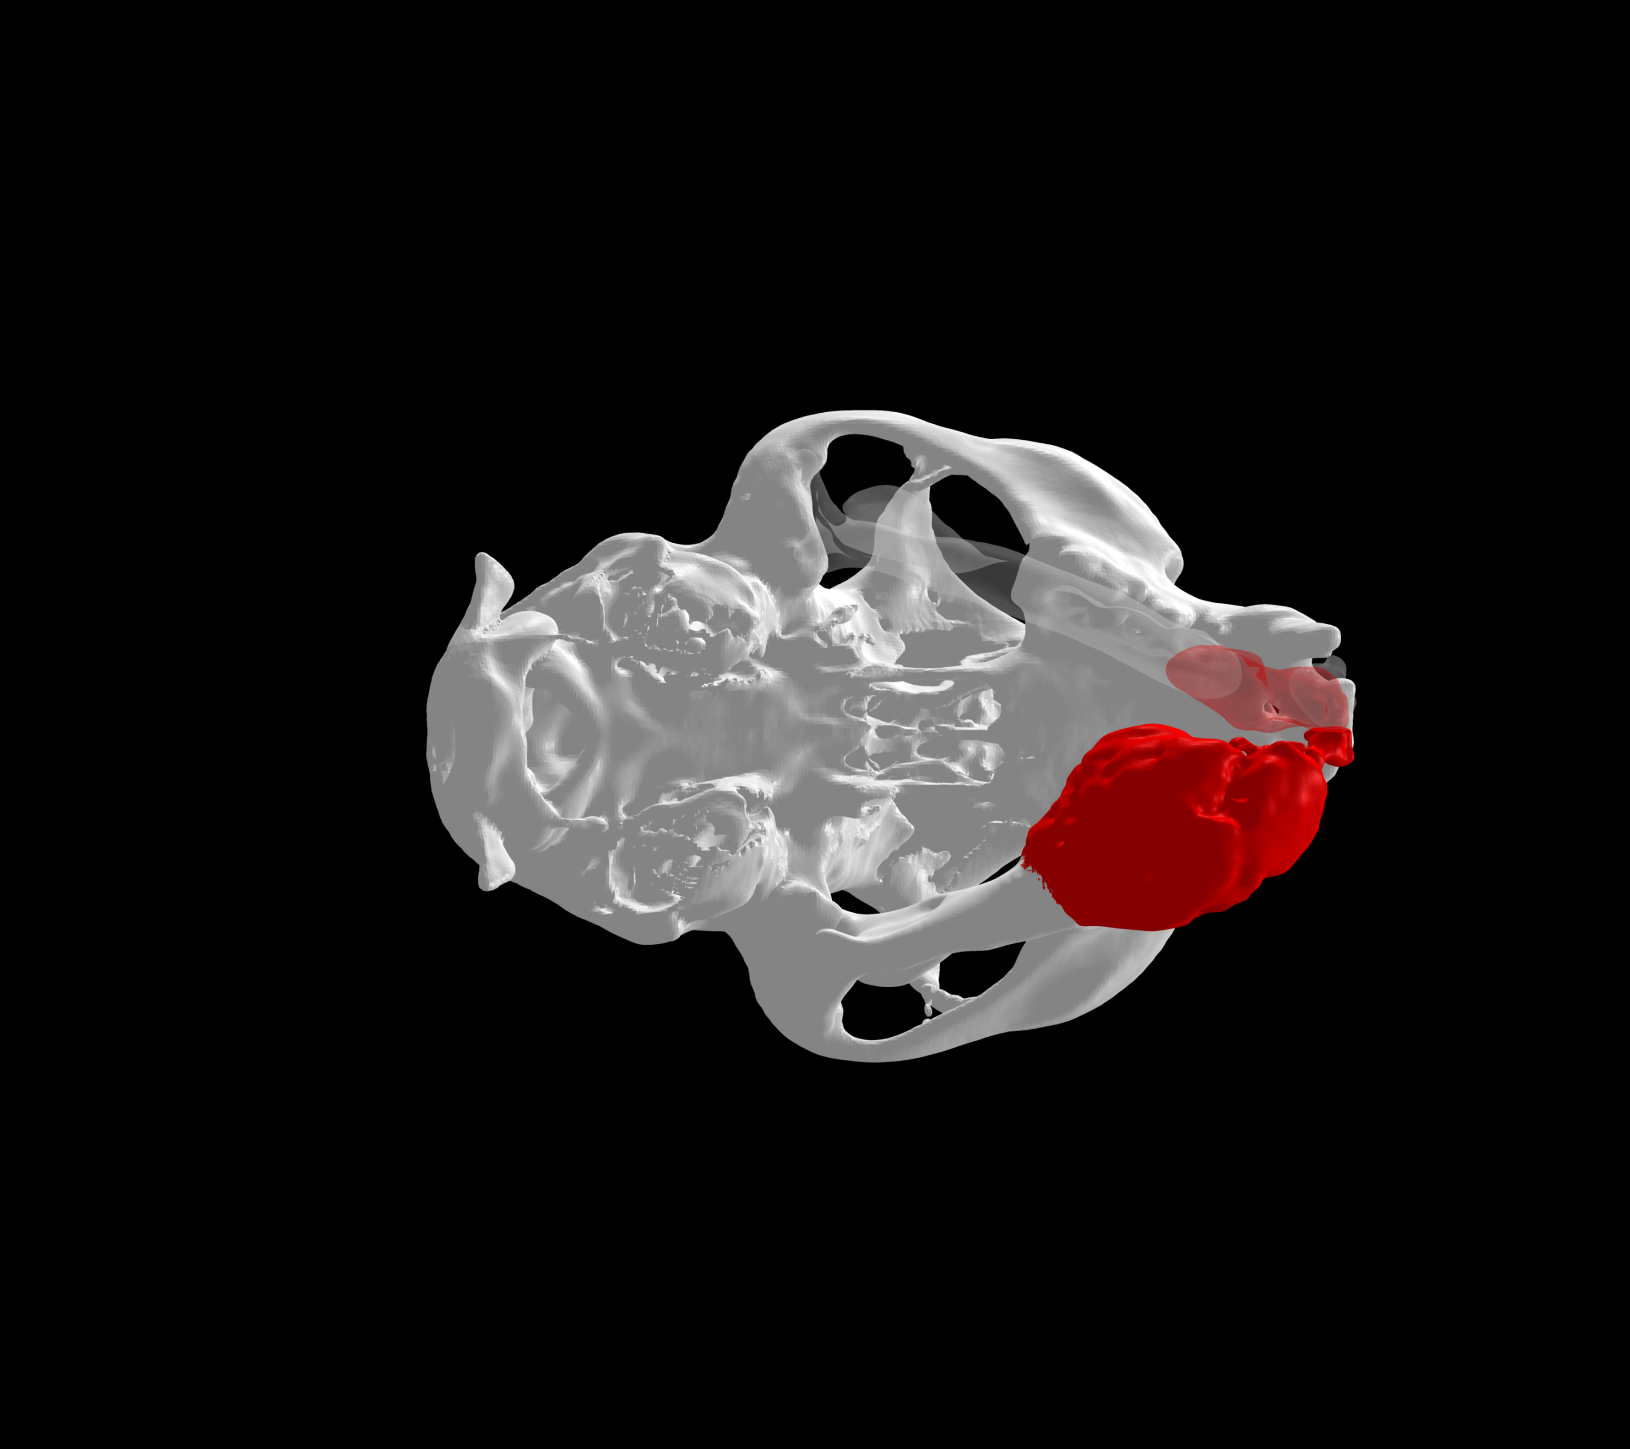

Esto se consigue gracias a los avances en la tecnología de fabricación, como la impresión 3D. Con esta tecnología se pueden crear implantes personalizados tanto en acero quirúrgico como en titanio a partir de imágenes médicas de tomografías computerizadas (TC) o resonancias magnéticas (RM).